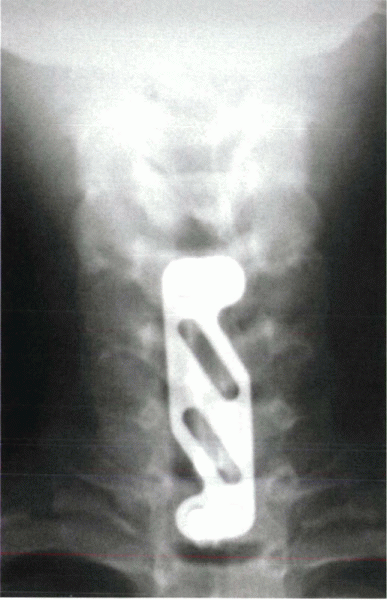

multiple-level discectomies but does not improve the fusion rate in

single-level anterior cervical discectomy and fusions. Plating should

be used for multiple-level interbody fusions, single-level fusions in

smokers, single-level fusions in which allograft is employed, and

pseudarthrosis repair. In practice, plating allows for a more

aggressive rehabilitation and decreased duration of immobilization (Fig. 14-8).

![]() |

|

Figure 14-6

Anteroposterior radiograph after a three-level anterior cervical discectomy and fusion with tricortical grafts for multiple-level herniations. The anterior plate assists with stability and improves fusion rates, especially in multiple-level operations. |